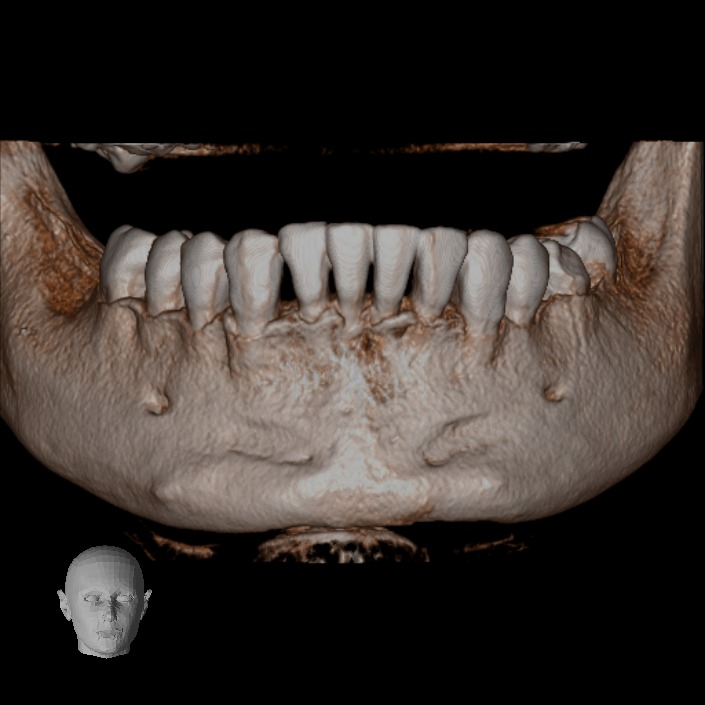

En nuestra clínica en Bogotá contamos con equipos de tomografía CBCT de última generación, que garantizan la más alta calidad en diagnóstico dental y permiten a tu odontólogo planificar cada detalle de tu tratamiento con máxima precisión.

• Rápido – Cómodo – Eficaz: Las imágenes obtenidas con nuestros equipos son altamente detalladas, mostrando los tejidos duros sin perder calidad.

Podemos analizar la posición y orientación de estructuras críticas como los nervios, las raíces dentales, los senos paranasales y la nariz, lo que ayuda a lograr un diagnóstico lo más preciso posible. Con nuestra tecnología de imagen avanzada, tu odontólogo podrá monitorear la estabilidad a largo plazo de tus restauraciones dentales, de esta forma se podrá obtener el resultado estético que deseas con tu tratamiento.